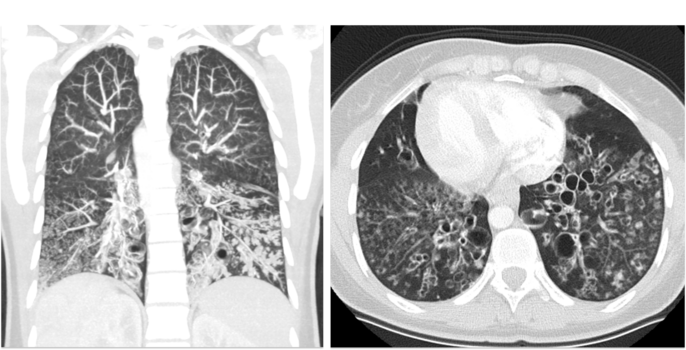

Identification of genetic causes for MMAF is rapidly increasing, whereas knowledge on molecular composition and function of associated components remains poorly understood. As sperm flagella and motile cilia comprise a similar axonemal structure, Primary Ciliary Dyskinesia (PCD), a mucociliary clearance disorder with recurrent airway infections, is closely associated with male infertility. Unfortunately, no evaluation of further disease manifestations, such as lung disease in MMAF males or fertility status of PCD males, is systematically performed.

Our recently published data and preliminary work demonstrate that several MMAF individuals additionally show a respiratory phenotype (e.g. SPEF2), and distinct PCD variants display MMAF (e.g. CCDC39). MMAF and PCD males will be recruited for critical genetic, andrological, and pulmonological evaluation and molecular characterization of human sperm flagella and motile cilia. Translation of study results into patient care will improve diagnostics and make aware potentially associated symptoms in MMAF and PCD with substantial benefit for the patient, if e.g. lung disease is treated properly.